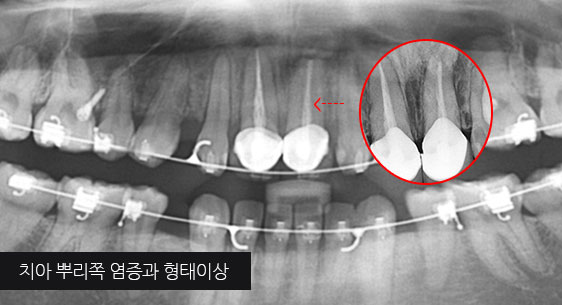

치아 뿌리 주변 염증과 치조골이 녹아내려 통증과 더불어 치아가 흔들리는 상태로 내원한 환자입니다. 우선 큐렛으로 잇몸 속 치석을 제거하였습니다.

뿌리 주변 염증은 신경관을 소독하고 약재를 삽입하는 신경치료를 시행하였습니다.

기존 신경치료는 양호한 상태이나 치근부위에 염증과 치조골 소실이 진행 중

기존 신경치료 부위에 염증과 치조골이 소실되고 있는 상태